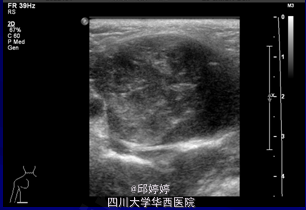

患儿,男,3岁。发现左侧臀部包块2月余。无发热,疼痛,黄疸,乏力、恶心、呕吐、腹痛、腹泻等表现。精神,饮食,睡眠,体重,大小便均无明显异常。

查体:左侧臀部近骶尾部触及一包块,大小约4x3cm, 边界清楚,形态较规则,质地较软,可活动,无压痛,无充血,水肿。腹股沟淋巴结未触及。双下肢肌力及运动功能未见异常。血清肿瘤标志物正常。 超声:左侧臀部近骶尾部皮下查见弱回声团,大小约40x34x33mm,边界清楚,形态规则,内部回声不均匀,内未见明显血流信号。 超声诊断:左侧臀部近骶尾部皮下弱回声团:畸胎瘤?

手术切除。术后病理诊断:<骶尾部>囊性成熟性畸胎瘤。